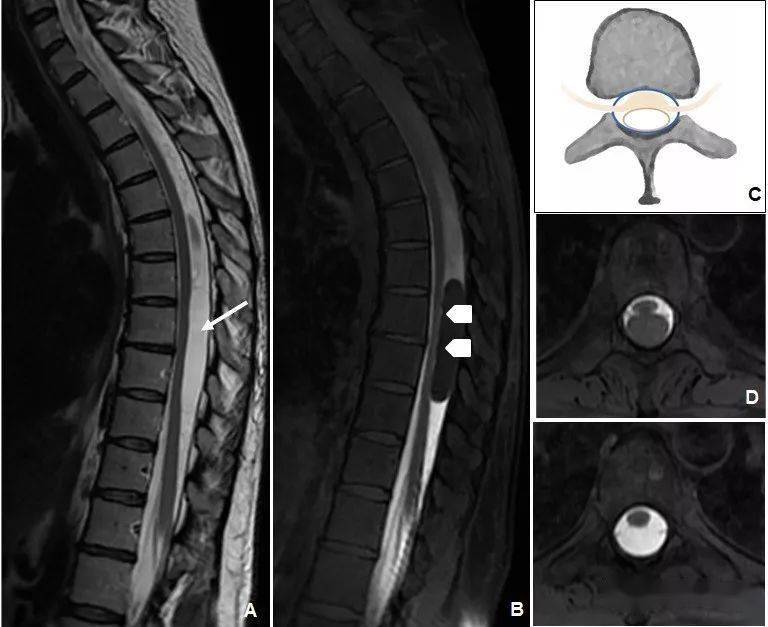

病例:胸7椎管内表皮样囊肿一例